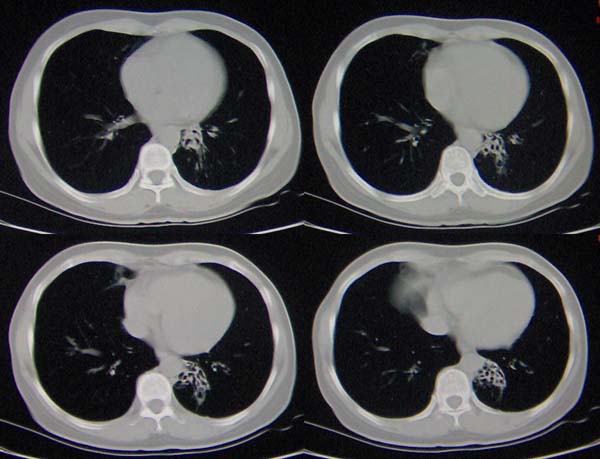

左肺下叶支气管呈囊状扩张。考虑支扩。

左下肺支气管扩张;支气管炎;左下肺纤维条索并局部胸膜肥厚。

左肺下叶支气管呈囊状扩张。考虑支扩。胸膜肥厚\\粘连,建议增强除外肺隔离症.

左肺上叶小片状病灶密度底,左下叶见多发小囊状病灶,周围透光增强无纹理,沿左侧膈肌旁见条带状病灶边界清晰,

1左肺上叶炎症,左下支气管扩张伴感染,肺隔离征待除外,2肺大泡,3左下叶内基底段不张?

左肺上叶舌段炎症,左肺下叶支气管扩张并感染

左肺舌叶及右肺下叶背段斑片状低密度影,左肺下叶内基底段网格状阴影,周围肺野透亮度增高,结合临床咳嗽、发热,38度,无咯血及反复感染病史,考虑双肺炎症,左下肺发育不良。建议抗炎治疗后复查或增强与左下肺隔离症鉴别。